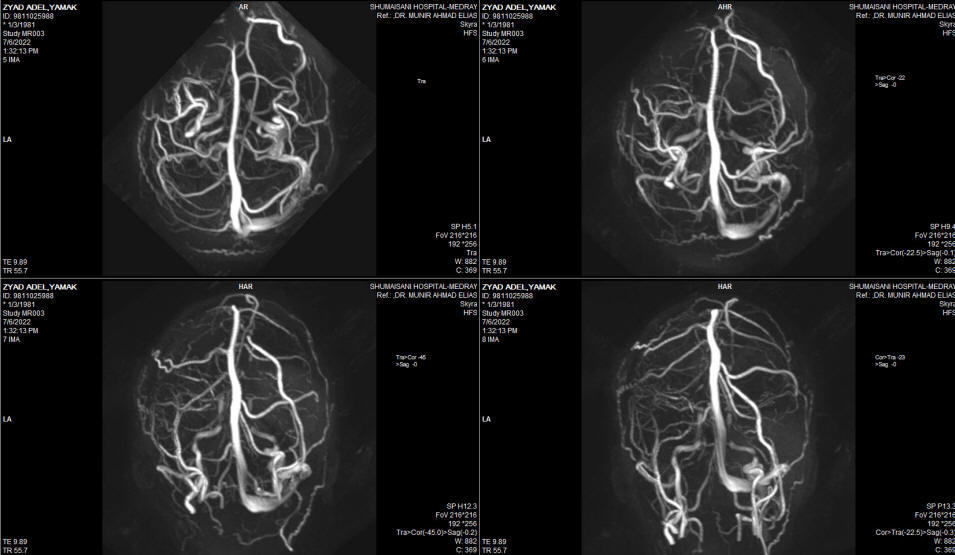

The patient then came 26-June-2002 complaining of double vision, complete hearing loss left side, but he walk without aid with almost complete recover of the left facial nerve. Still complaining of swallowing difficulty, but he mention that the assort of the eating food is widening, but still using PEG.  MRI of the brain done 06-July-2022 showing massive malacia of the left cerebellar hemisphere. The brain stem and the posterior circulation are intact. The MRV showing absent left transverse sinus , which could be a variant. The left trigeminal nerve is not compressed and the canal is wide.

Fig:-4 MRA of the brain with excellent posterior circulation.